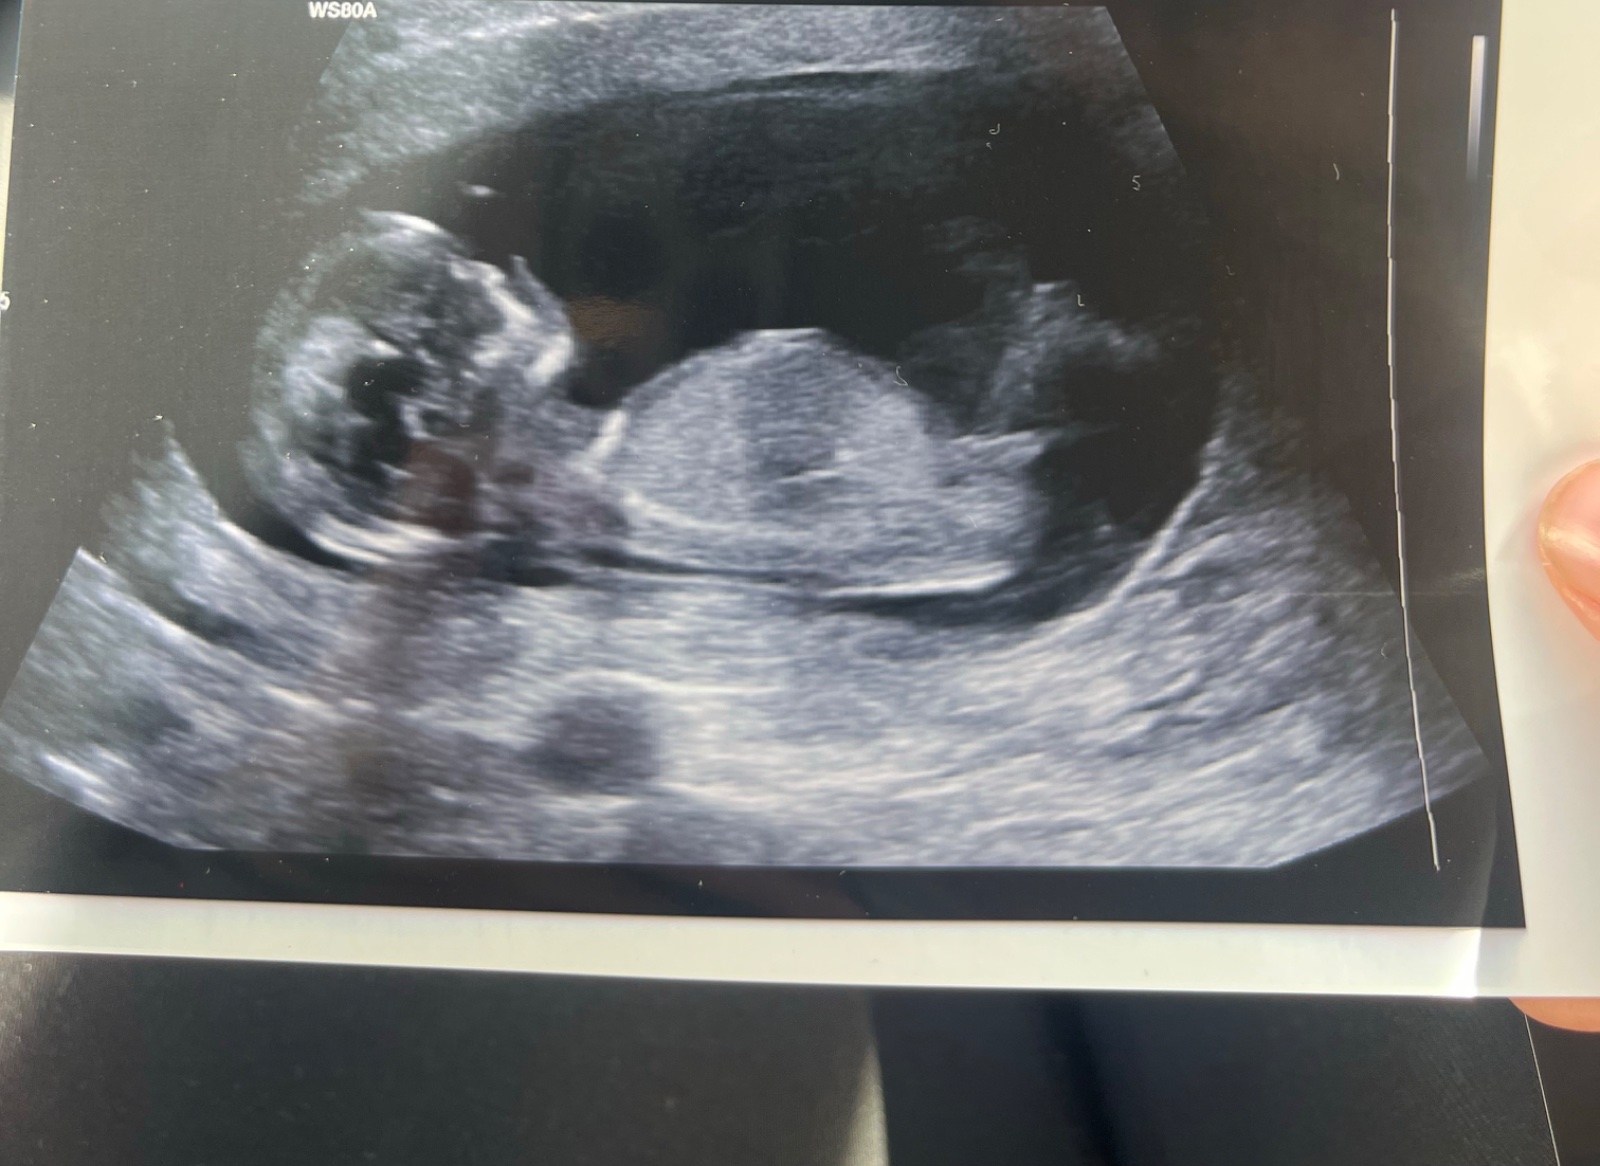

Ahoj holky, doktorka nám nechtěla říct pohlaví , že to rika az na druhým screeningu, poznáte někdo? Dekuji

Holčička

Tak od doktorky 90% holčička

@vikynat myslím, že holčička